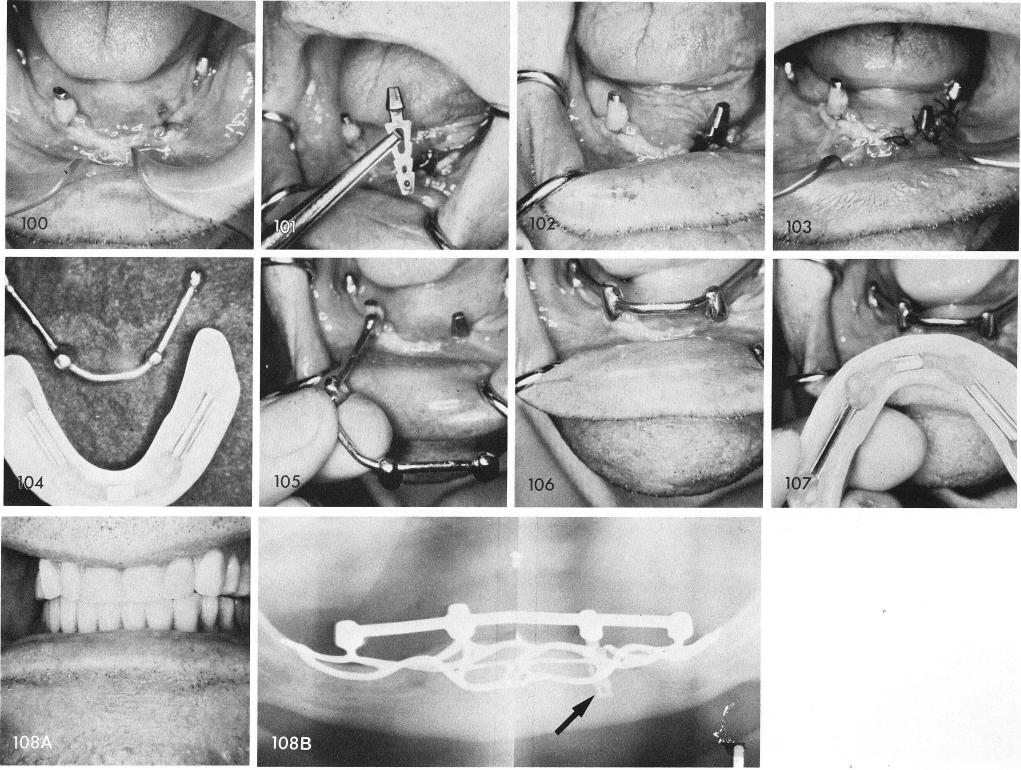

Because of poor implant design with exceptionally long necks at the expense of shorter posts, the left neck of the cuspid implant snapped off from its base and it was decided to build up the right neck with a very hard acrylic for more support and better denture support, fig. 100. A blade-vent was inserted into the bone in the same area where the left neck broke off, figs. 101, 102, 103, and impressions of the three subperiosteal implant posts and the blade post was taken to fabricate a Dolder bar and coping structure to splint the isolated blade to the three remaining posts and give support to the new denture with the aid of internal clips, figs. 104, 105, 106, 107, 108A. The entire case is in for 12 years, the blade with new superstructure is in for seven years. Post-operative x-ray, fig. 108B.

1 Mandibular bladevent insertion in area of previous implant fracture